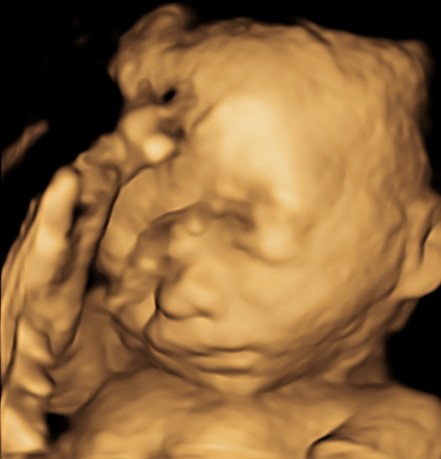

Il tesoro in ecografia è sempre più bello, infatti è da questo mese, ma soprattutto dal prossimo che comincerà ad ingrassare e diventare più tondetto per la gioia degli occhi di babbo e mamma!